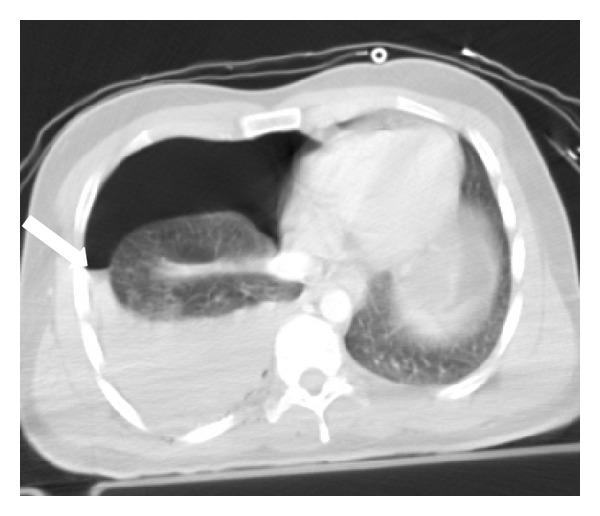

Imaging plays an essential part of chest trauma care. By definition, the employed imaging technique in the emergency setting should reach the correct diagnosis as fast as possible. In severe chest blunt trauma, multidetector computer tomography (MDCT) has become part of the initial workup, mainly due to its high sensitivity and diagnostic accuracy of the technique for the detection and characterization of thoracic injuries and also due to its wide availability in tertiary care centers. The aim of this paper is to review and illustrate a spectrum of characteristic MDCT findings of blunt traumatic injuries of the chest including the lungs, mediastinum, pleural space, and chest wall.

影像学在胸部创伤治疗中起着至关重要的作用。根据定义,在急诊环境中所采用的影像学技术应尽快得出正确诊断。在严重胸部钝性创伤中,多排螺旋计算机断层扫描(MDCT)已成为初始检查的一部分,这主要归因于该技术在检测和鉴别胸部损伤方面具有高敏感性和诊断准确性,还归因于其在三级医疗中心广泛可用。本文旨在回顾并阐述胸部钝性创伤包括肺、纵隔、胸膜腔和胸壁的一系列MDCT特征性表现。